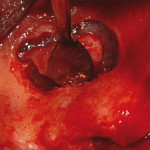

Ematoma del pavimento della bocca

L'accumulo di sangue in un'area tissutale circoscritta (ematoma) e/o l'effusione ematica a livello dei tessuti di superficie (ecchimosi) sono complicanze di norma non comuni...